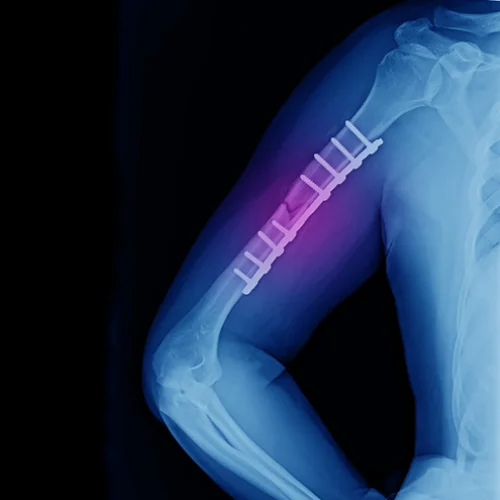

Hand and wrist surgery focuses on the diagnosis, treatment, and rehabilitation of conditions affecting the hand, wrist, and forearm. Whether caused by injury, arthritis, or repetitive strain, our expert orthopedic surgeons provide advanced surgical and non-surgical solutions to restore function, alleviate pain, and improve mobility.